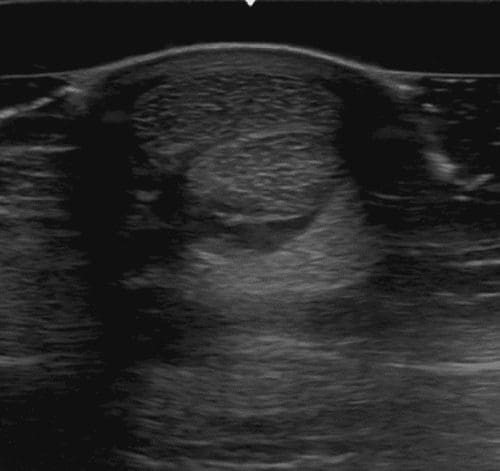

However, this can sometimes be turned to our advantage. One of the important parts of the assessment of the tendinous and ligamentous structures in the distal part of the equine limb is checking the integrity of the borders of those structures, and deliberately imaging them in an off-incidence manner (just a few degrees are necessary) will result in the tendons and ligaments appearing more hypoechoic than ‘normal’, but the borders of those structures remain bright and thus appear relatively hyperechoic (and so stand out – see Fig.1).

Fig. 1 SDFT and DDFT in the distal metacarpus, scanned on-incidence (A) and off-incidence (B); notice the reduced echogenicity of the tendon fibres in B, resulting in an apparent hyperechogenicity of the borders (outline) of the tendons. Images courtesy of Marcus Head, Rossdales Diagnostic Centre.